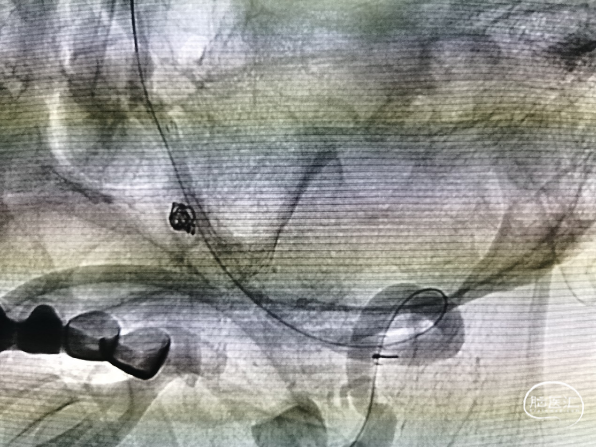

穿支架网眼动脉瘤近全栓塞(Target 360 Ultra 3 mm×6 cm、Target 360 Ultra 2 mm×6 cm

Gateway 2.0 mm×15 mm球囊命名压缓慢后扩支架